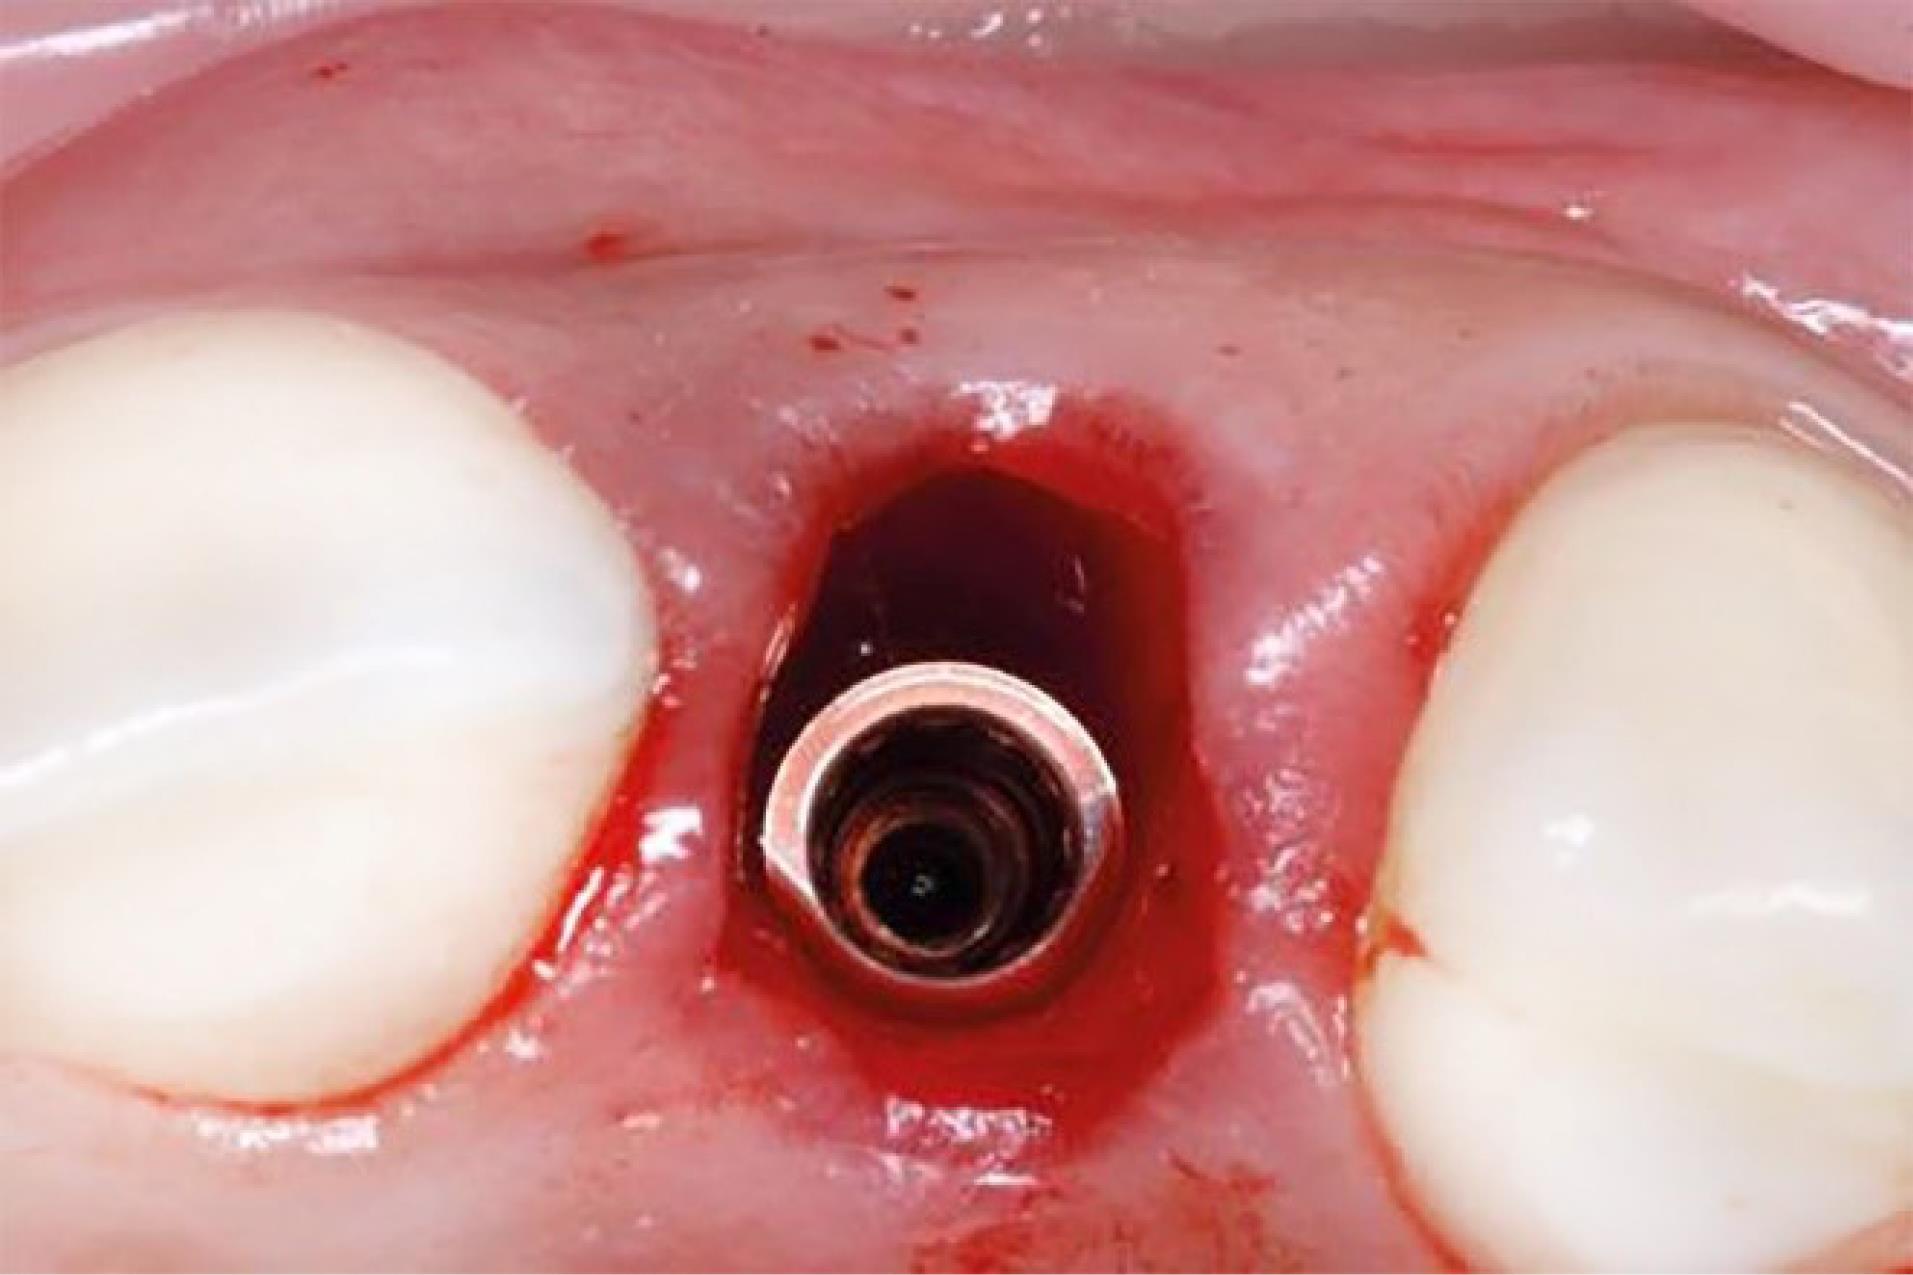

Figure 3.

Implants placed in fresh extraction sockets

One oral and maxillofacial surgeon with ten years of experience (the operator) performed all the surgical procedures. In both groups, after selecting the patients based on eligibility criteria (Figures 1 and 2), local anesthesia was performed by injecting 2% lidocaine (with 1:80 000 adrenaline). After cutting the crestal, elevating a mucoperiosteal flap, and extracting the tooth without trauma, the bone-level implant recipient site was prepared under cooling with a physiological serum solution according to the manufacturer’s protocol (Dio, Seoul, Korea). For all implants, a speed of 15 rpm with a torque of 35-40 Ncm was used. The diameter of the implants was chosen so that at least 1 mm of bone remained on both buccal and palatal aspects after implant placement. For vertical positioning, the implant was also positioned at the level of the buccal bone crest (Figure 3). The implant was placed, and the area was sutured. The sutures were removed seven days after surgery. After the surgery, all the patients received amoxicillin (1.5 g) or clindamycin (1.8 g) daily for three days and a non-steroidal anti-inflammatory drug for pain relief, in association with mouthwash. The patients also received advice regarding oral hygiene. No temporary dentures were placed during the 6-month follow-up period.